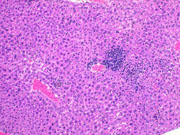

The left image shows a focus of necrosis with an early inflammation cell infiltration at the periphery of the necrotic hepatocytes. In the right image, the inflammatory reaction is more pronounced.